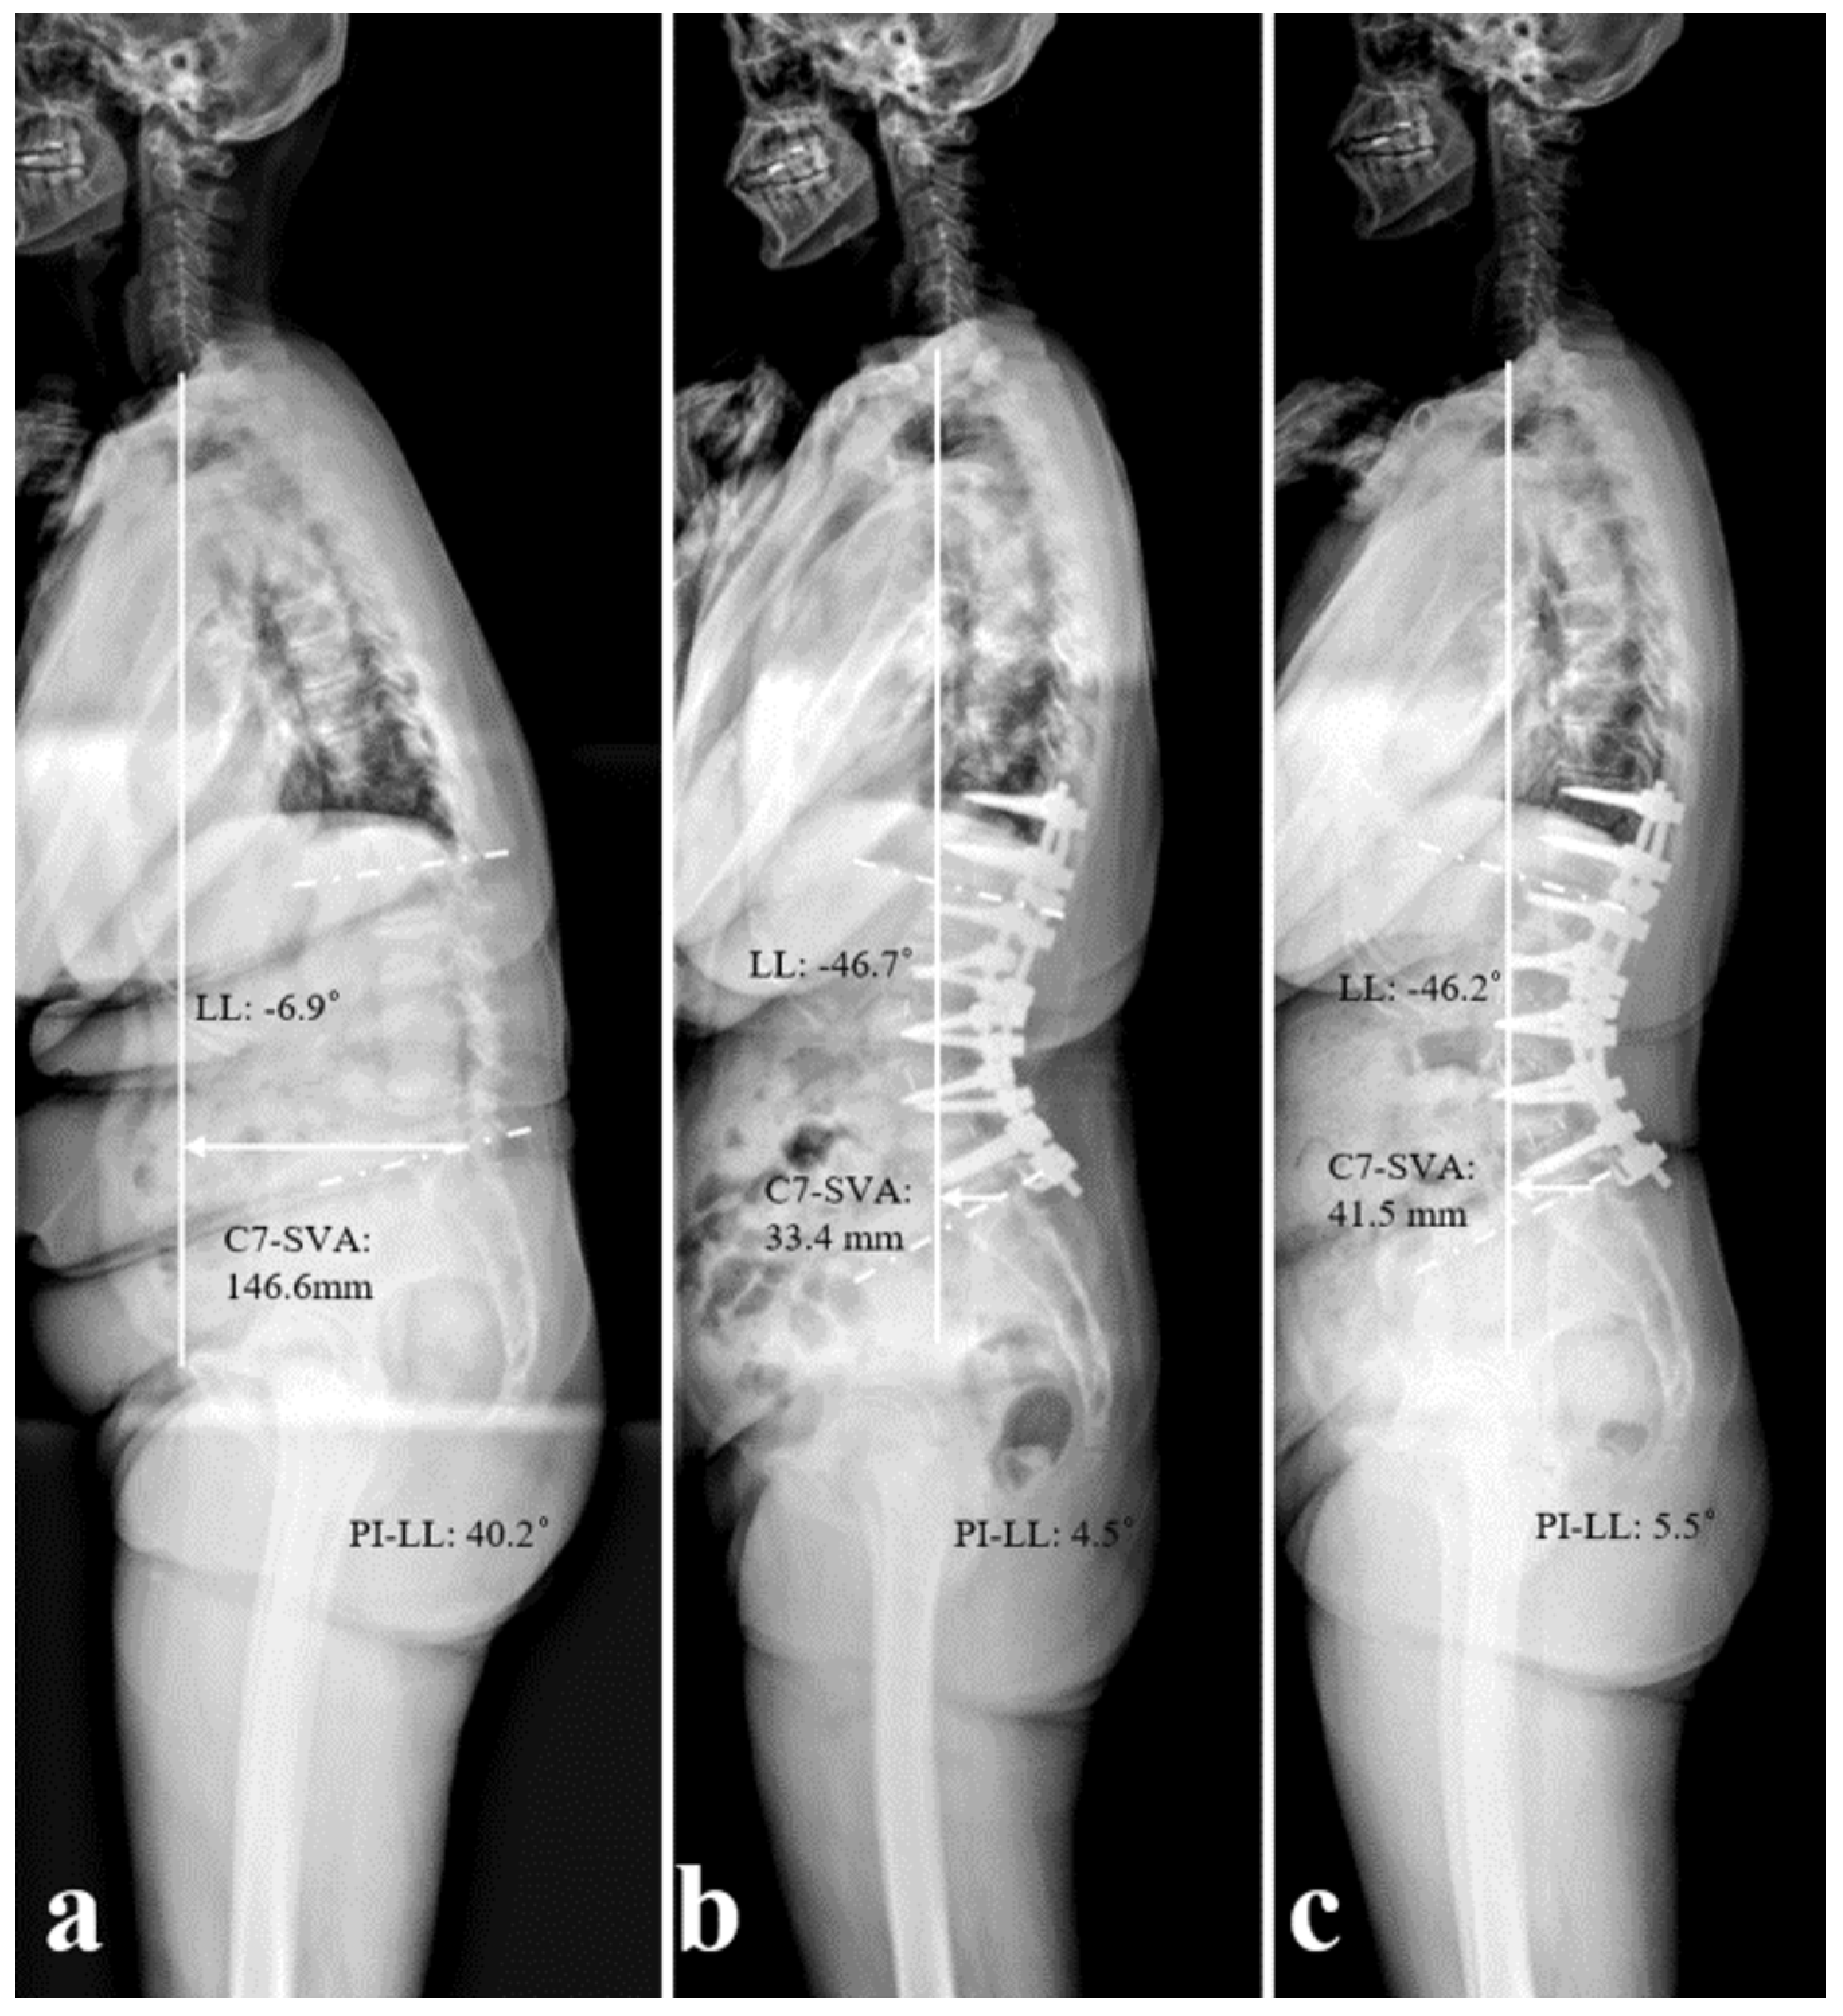

| C7 SVA (mm) | Preop. | 174.6 ± 45.5 | 52.9 ± 65.1 | 0.011 * |

| Immed. postop. | 38.1 ± 45.3 | 23.8 ± 35.4 | 0.412 | |

| 2 years postop. | 49.4 ± 33.8 | 54.5 ± 64.3 | 0.584 | |

| Change | −136.2 ± 68.6 | −29.3 ± 75.8 | 0.018 * | |

| LL (°) | Preop. | −11.6 ± 19.3 | −22.8 ± 23.6 | 0.029 * |

| Immed. postop. | −52.1 ± 10.3 | −48.2 ± 17.7 | 0.299 | |

| 2 years postop. | −46.9 ± 11.2 | −43.3 ± 20.9 | 0.322 | |

| Change | −40.5 ± 15.4 | −25.4 ± 21.3 | 0.021 * | |

| PI-LL (°) | Preop. | 44.4 ± 17.5 | 29.1 ± 21.2 | 0.041 * |

| Immed. postop. | 3.9 ± 9.3 | 4.3 ± 6.6 | 0.551 | |

| 2 years postop. | −10.51 ± 5.5 | −15.42 ± 9.72 | 0.551 | |

| Change | −40.5 ± 15.3 | −24.8 ± 21.4 | 0.034 * |